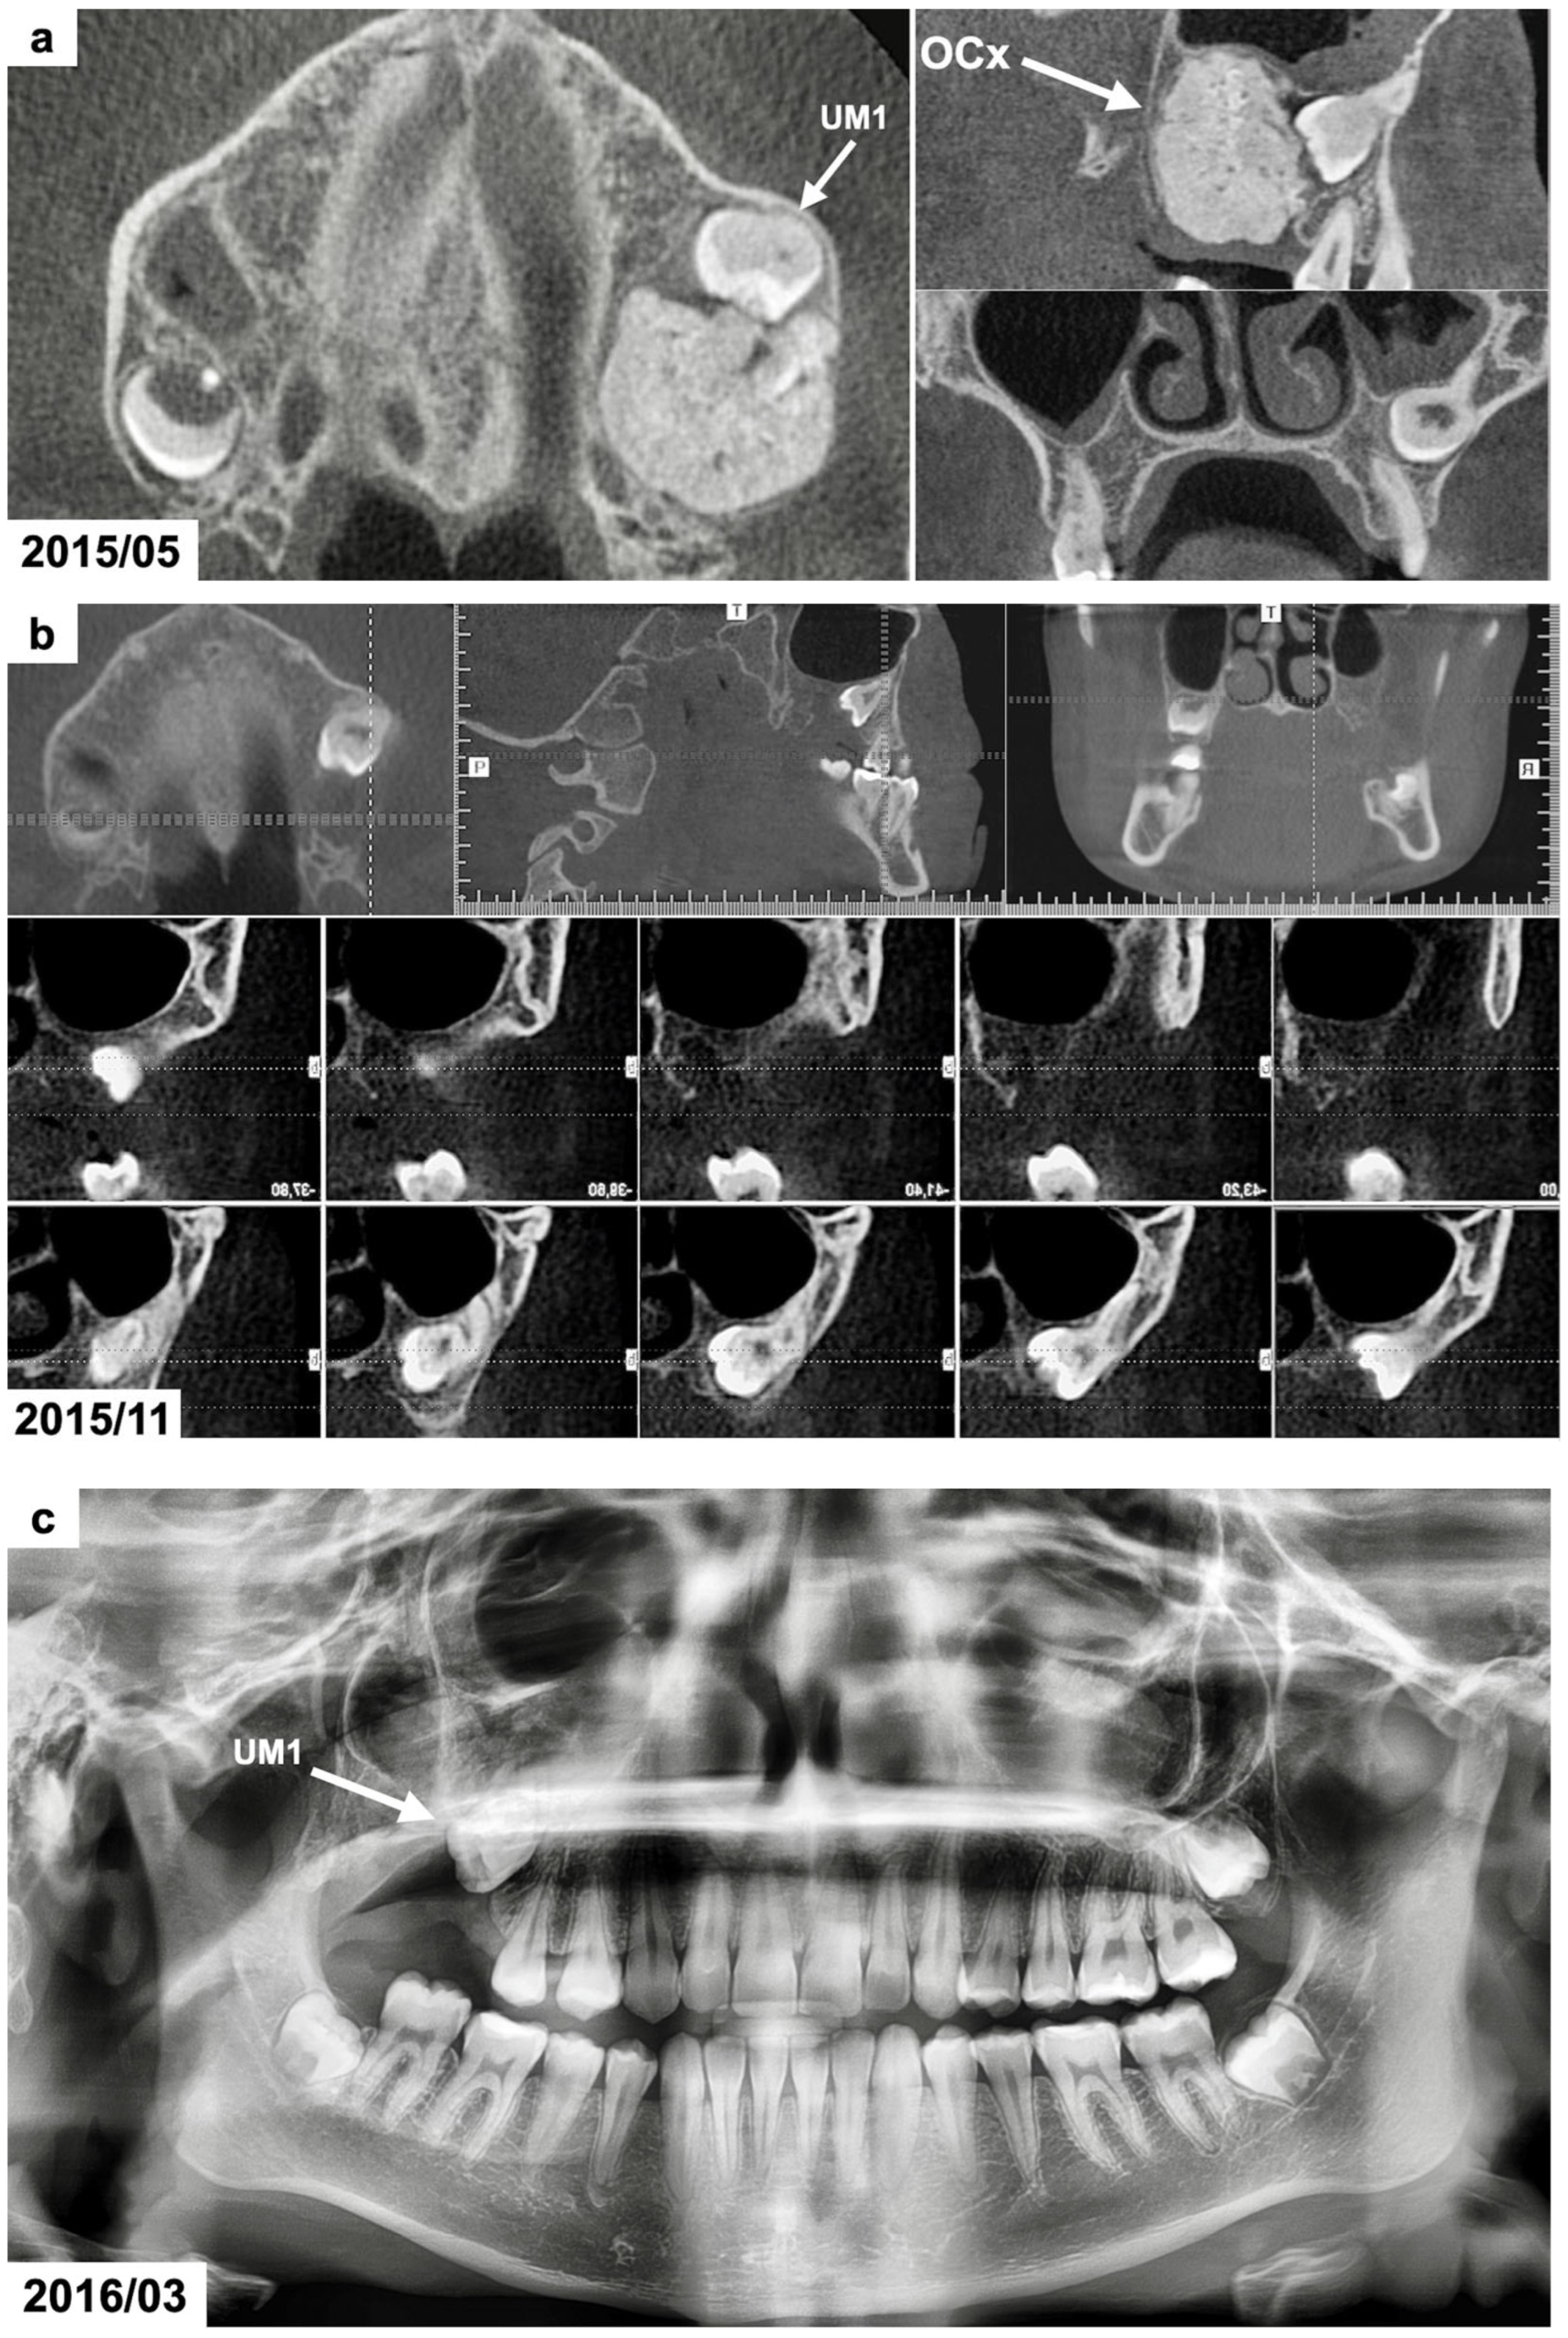

The panoramic radiograph (provided by the patient) revealed the presence of a radiodense lesion surrounded by a narrow radiolucent zone at the posterior area of the right maxilla, which was the suspected reason for the impaction of the right maxillary first permanent molar (Figure 2a).

Figure 2.

(a) CBCT examination scans before the treatment presenting the odontogenic tumor in the right maxillary molar region. The patient was 15 years and 10 months old. (b) CBCT examination scans after the surgical removal of the tumor presenting the malposition of the impacted permanent upper right first molar. The patient was 16 years and 4 months old. (c) Panoramic radiograph after the treatment, presenting the impacted maxillary. The patient was 16 years and 7 months old. (d,e) Intraoral photographs 10 months after the surgical treatment before the use of orthodontic traction with a segmented fixed appliance. The patient was 16 years and 7 months old. (f) Intraoral photographs 1 year and 4 months after the orthodontic traction of the permanent upper right first molar. The patient was 17 years and 10 months old. (g) Panoramic radiograph 6 years after the surgical and orthodontic treatment. The patient was 24 years and 1 month old. (h) Intraoral photographs 6 years after the surgical and orthodontic treatment showing the erupted permanent upper right first molar and its position in the dental arch. The patient was 24 years and 1 month old. (i) CBCT examination scans 6 years after the surgical and orthodontic treatment presenting the erupted permanent upper right first molar and the absence of the alveolar bone at the site of the tumor removal. The patient was 24 years and 1 month old.

Cone-beam computed tomography (CBCT) was scheduled to determine the dimensions and position of the tumor. The CBCT examination showed a focal area with spherical radiopaque mass resembling the radiodensity of irregularly composed hard dental tissues/dentin and enamel tissues surrounded by a thin radiotransparent rim in the right maxillary molar region (Figure 2b). The dimensions of the lesion were 16 × 18 × 20 millimeters. The roots of the maxillary first permanent molar were fully developed. The tooth was impacted at distoangular position and its crown occlusally contacted with the tumor. The maxillary right second and third molars were absent. Based on the CBCT examination, the presence of a complex odontoma was suspected.